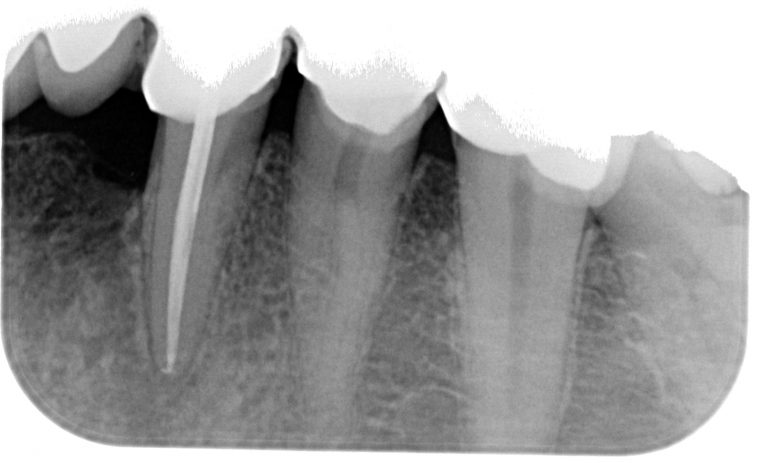

Endodoncia

Estos tratamientos realizados por un especialista, permiten conservar el propio diente del paciente, sin necesidad de extraerlo, siempre que sea posible.

Agunos de nuestros trabajos

A continuación mostramos algunos de nuestros trabajos antes y después del tratamiento.

Esta especialidad trata la necrosis de la pulpa dental. Una caries profunda que afecta al nervio de una pieza dental produce casi siempre dolor y si no es tratado a tiempo dará origen a un granuloma o un quiste en el maxilar.